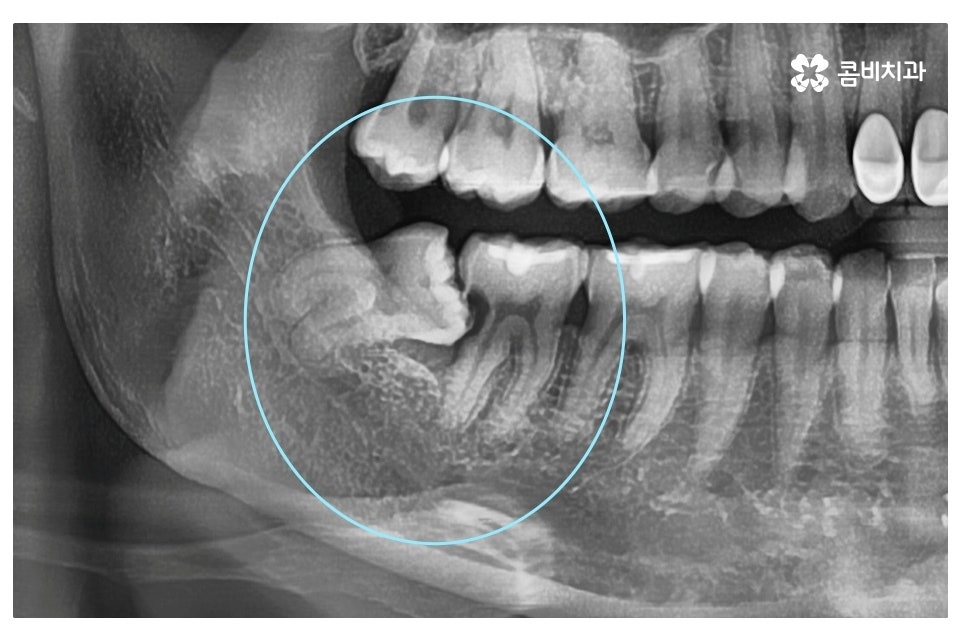

대표적으로 발치를 해야 하는 케이스는 사랑니가

누워서 자라면서 어금니 혹은 잇몸에 안 좋은 영향을

주는 경우이며 사랑니에 충치가 발생한 경우,

잇몸에 염증을 유발하는 경우 등이 있어요.

사랑니가 누워서 자라는 경우에 어금니 사이에 음식물이 끼기 쉽고

매복된 사랑니가 누워서 자라는 경우에는 눈으로는 상태를

확인할 수 없기 때문에 통증이나 불편한 증상을 느끼고

치과를 찾는 경우에 이미 치료가 늦는 경우가 많으며

이번 케이스처럼 멀쩡한 어금니까지 손상이 발생하는 경우도 있어요.

엑스레이 사진에서 보시는 것처럼 사랑니로 인해 어금니 옆 부분에

충치가 발생되었고 사랑니 발치 후 어금니 신경치료를 하여

자연치아의 손상이 커진 케이스라고 할 수 있는데요